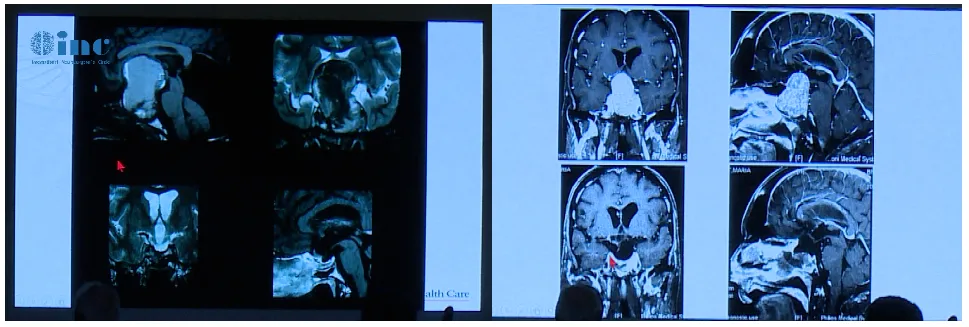

INC国际神经外科医生集团旗下组织世界神经外科顾问团(WANG)成员、世界神经外科学院主席William T.Couldwell教授在2019年第二届神经外科学术交流年会上Couldwell教授展开关于《巨大垂体瘤手术的细微差别》的学术演讲,分享了巨大垂体瘤的技术探讨和临床经验交流,其中不乏一些极具启发意义的罕见病例。

Couldwell教授演讲中展示的部分巨大垂体瘤

巨大垂体瘤手术成功切除关键:个体化选择手术入路及案例分享